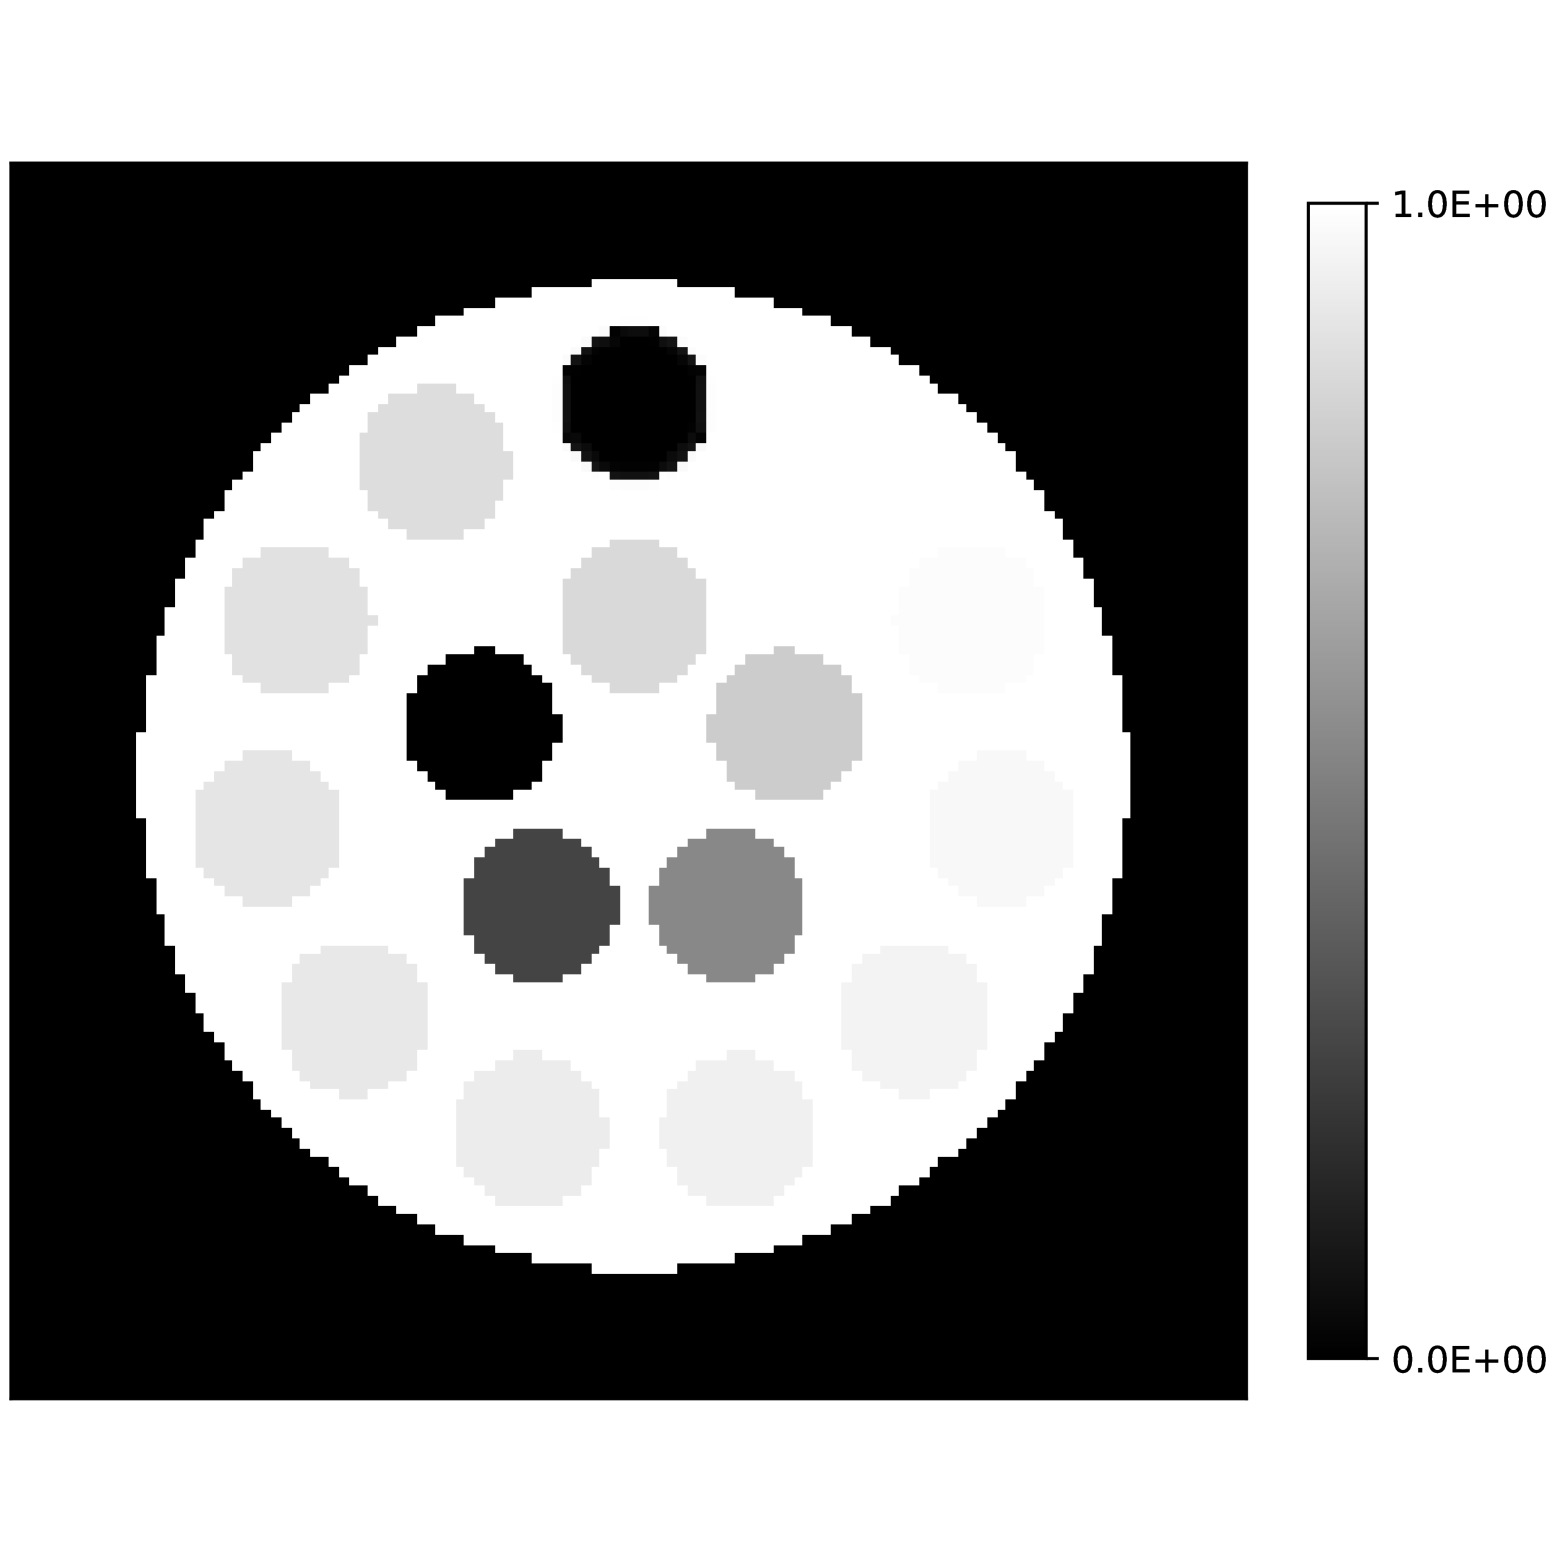

Our theoretical results show that generic concentrations and maps can be recovered exactly even when the fieldmap is not identifiable. To illustrate the impact of this fact, we perform a recovery experiment on a water (Fig. 2(a)), fat (Fig. 2(b)) and silicone (Fig. 2(c)) in silico phantom. The concentrations are all real. The values for the fieldmap and used to generate the signal are shown in Figs. 2(d) and 2(e). The echo times have the form where ms and ms with .

We solve (23) using projected gradient descent as initial iterate a vector with all components equal to one. Forward finite-differences were used to compute the gradient. The bound on the norm of the gradient is Hz at voxels with non-zero signal magnitude, and kHz at voxels with zero signal magnitude. This avoids imposing artificial constraints at voxels with no signal. The step size used is and the termination conditions

In Figs. 2(f), 2(g) and 2(h) show the recovered concentrations of water, fat and silicone, and Fig. 2(j) shows the recovered . These recovered quantities are all qualitatively similar to their true values. In contrast, Fig. 2(i) shows the recovered fieldmap, which differs from its true value. By comparing the errors in the recovered concentrations, we see that they are within a reasonable accuracy except in regions with a large magnitude for the fieldmap gradient, indicating a bound that is too small (Figs. 2(k), 2(l) and 2(m)). A similar behavior is seen in the recovered (Fig. 2(o)). The error for the recovered fieldmap tends to be larger outside the area of the phantom (Fig. 2(n)).